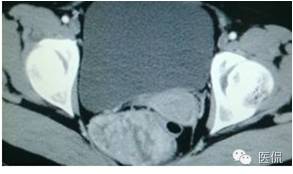

CT平扫(CT值23HU)